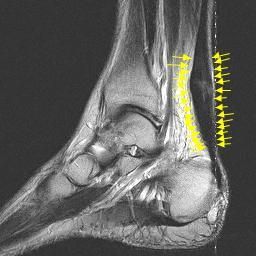

Η τενοντίτιδα Αχιλλείου Τένοντα μπορεί να είναι οξεία ή χρονία. Διακρίνεται σε τρεις τύπους:

- Insertional Achilles tendonitis

- Retrocalcaneal bursitis & Haglund deformity

- Achilles Tendonitis